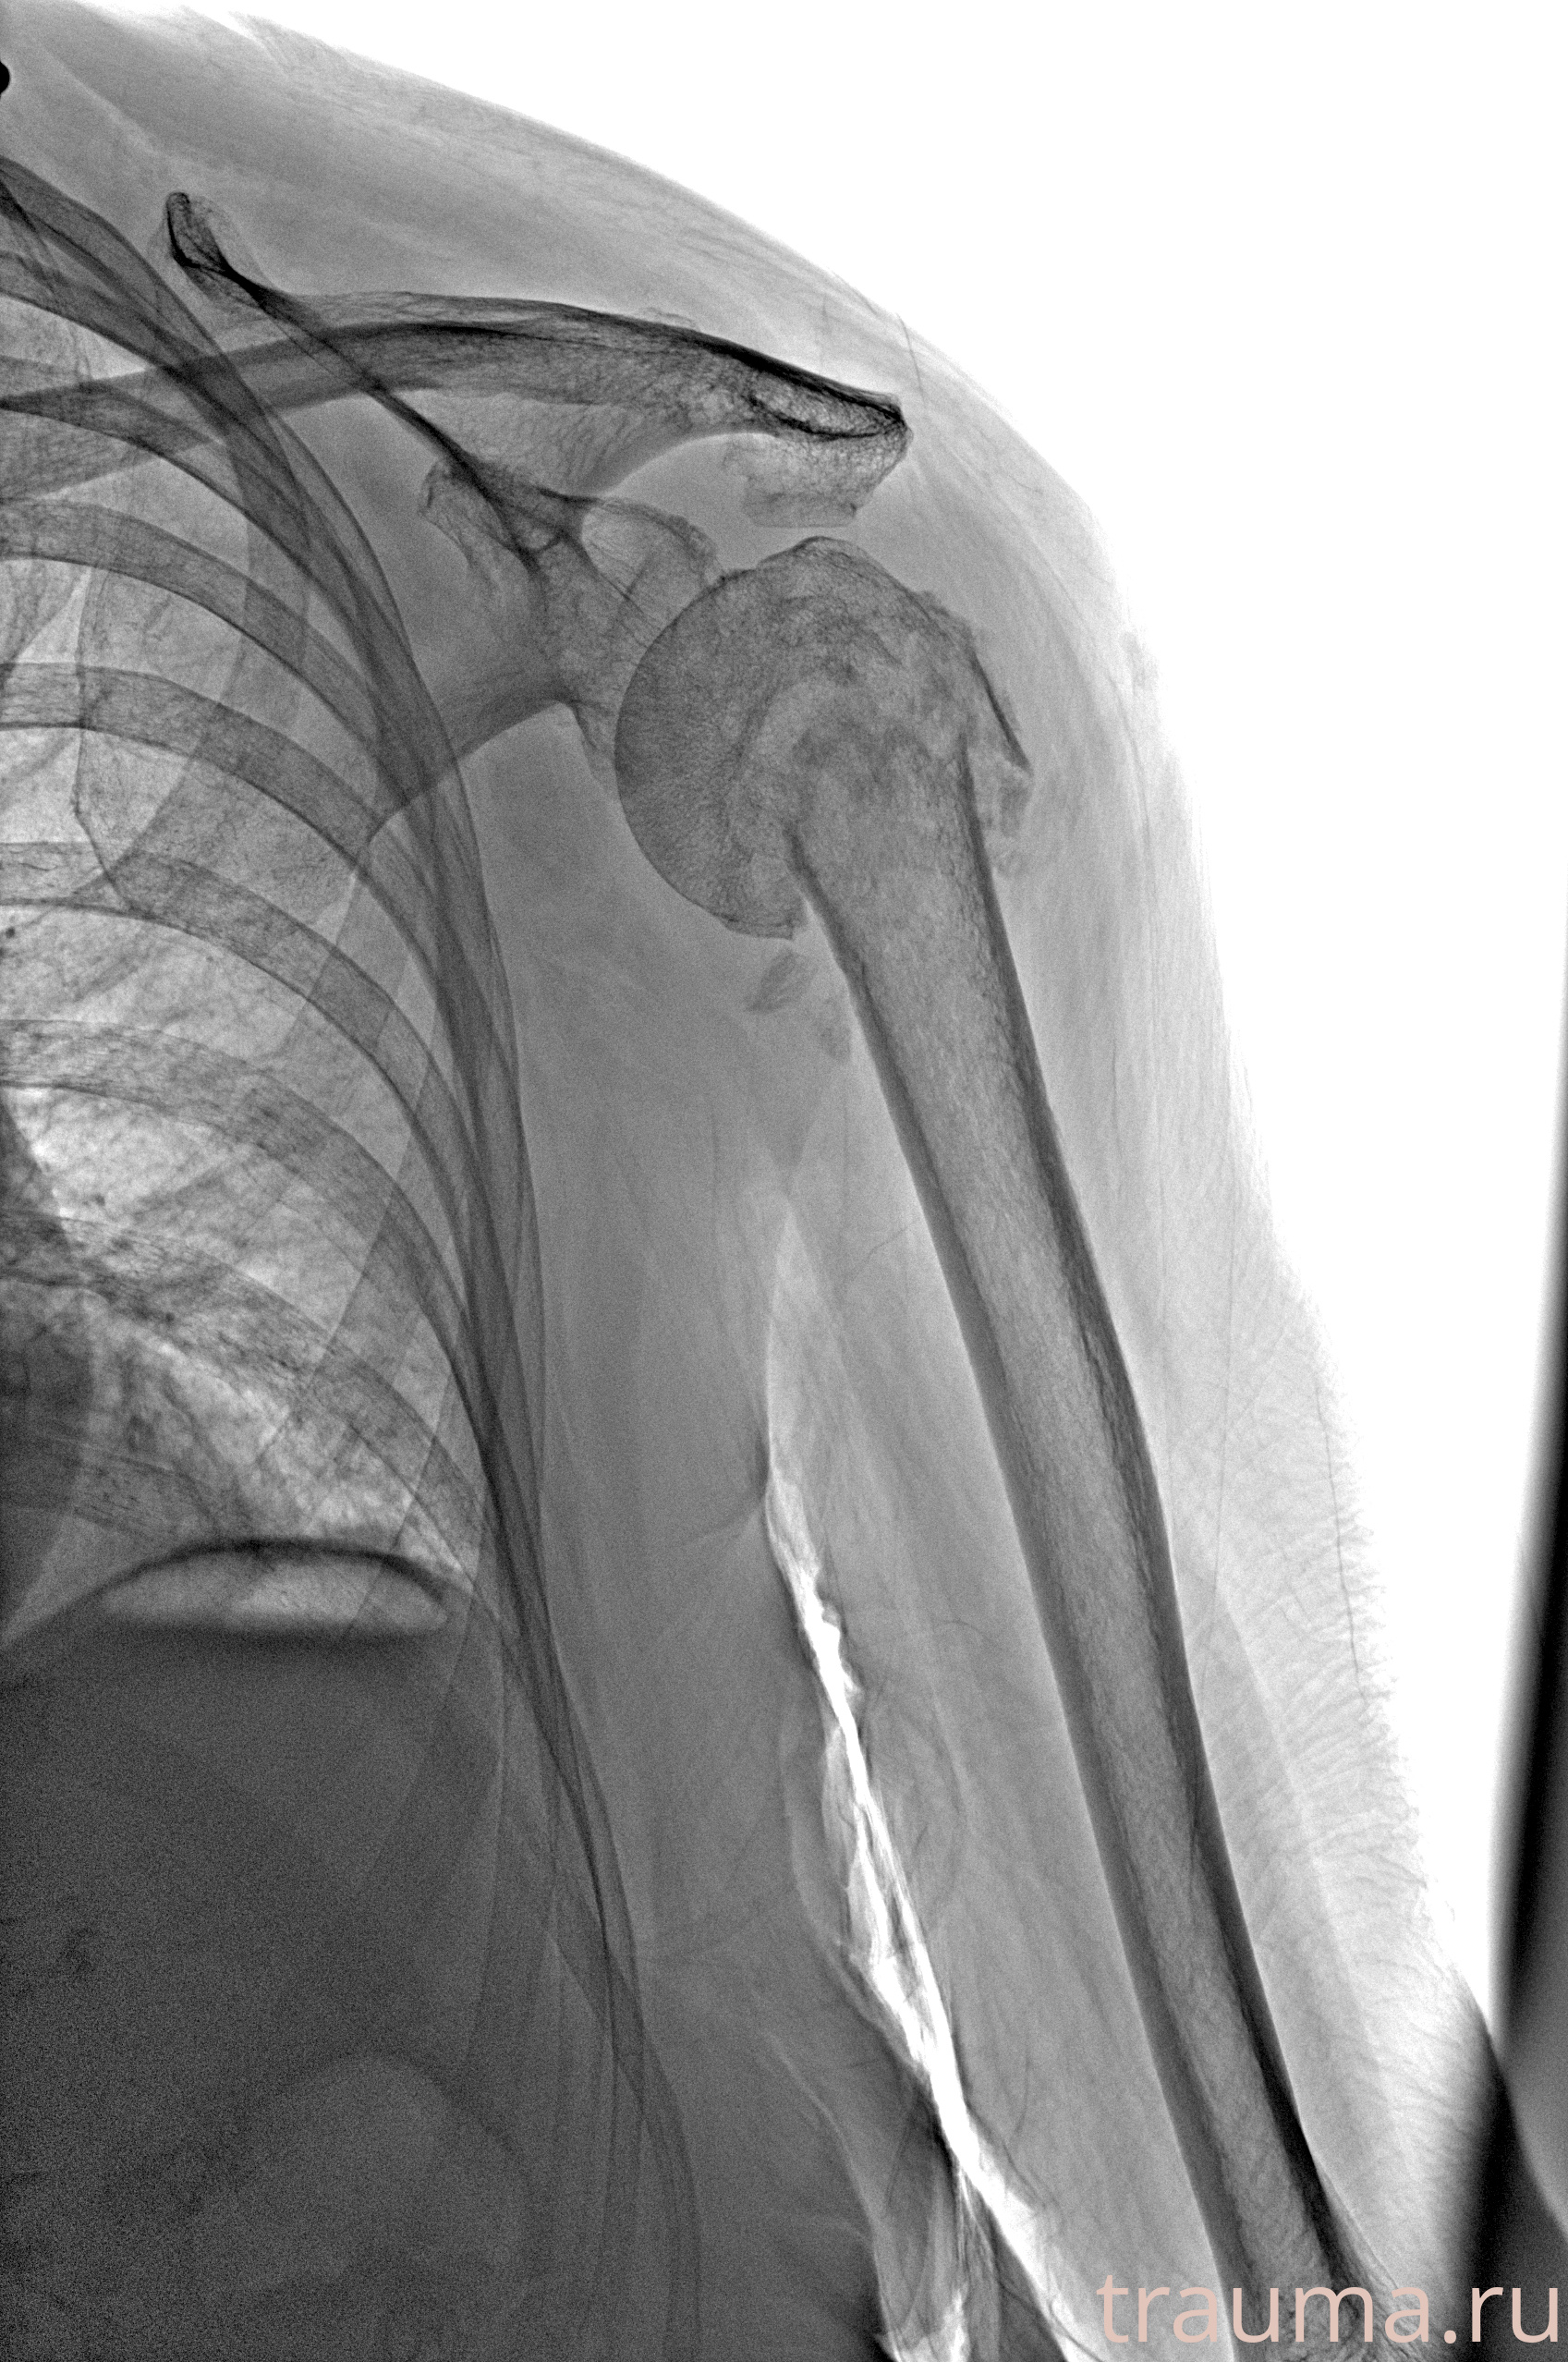

Рентген на дому: по вашему адресу приезжает врач-рентгенолог, травматолог-ортопед с мобильным рентгеновским аппаратом, проводит диагностику травмы или заболевания, делает необходимые рентгенограммы, дает рекомендации по дальнейшему лечению. Получить качественные снимки в домашних условиях возможно благодаря уникальной методике, разработанной МосРентген Центром для института  Склифосовского